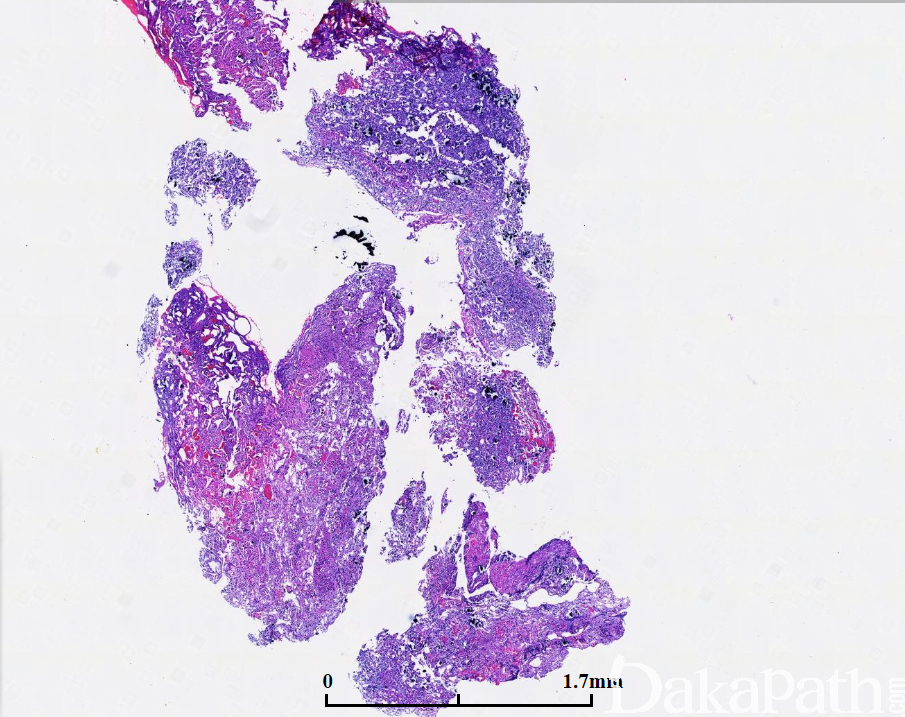

组织学表现为大的不规则细胞巢、梁状、实性细胞巢、乳头状及菊型团结构都有可能出现,可以以一种或两种结构为主;

细胞常叫正常细胞大,也可能比正常细胞小,可呈嗜碱性、嗜酸性或嫌色性改变,多数呈圆形、多边形或偶见细长形伴圆形至卵圆形胞核,细致点状染色质,核仁不明确及中量胞浆,少数可见不典型及核分裂,甚至出现多形性、坏死等,但都不足以诊断恶性。